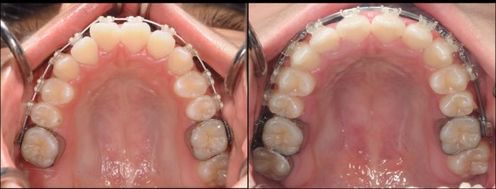

混合歯列から拡大装置を使用し、ワイヤーでの矯正に移行した症例。

天然歯を抜歯することなく、歯列不正を改善できた。

(左上は初診時、右上は拡大床セット時、左下は永久歯列に移行した時期、右下現在)